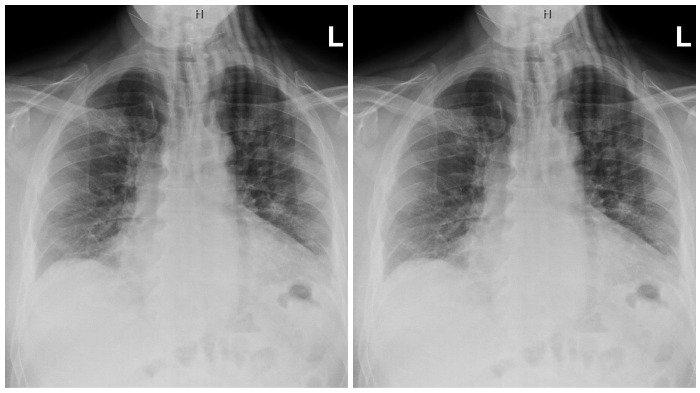

Sebuah penelitian terhadap paru-paru orang yang meninggal dunia karena Covid-19 telah menemukan kerusakan paru-paru persisten dan ekstensif dalam banyak kasus.

Tim peneliti menganalisis sampel jaringan dari paru-paru, jantung, hati, dan ginjal dari 41 pasien yang meninggal dunia karena Covid-19 di Rumah Sakit Universitas Trieste Italia antara Februari dan April 2020.

Dalam sebuah wawancara telepon, Mauro Giacca mengatakan, sementara tim peneliti tidak menemukan tanda-tanda infeksi virus atau peradangan berkepanjangan pada organ lain.

Akan tetapi, mereka menemukan "kerusakan yang sangat besar pada anatomi paru-paru", dengan jaringan sehat "yang hampir seluruhnya digantikan oleh jaringan parut atau keloid (scar tissue)."

KERUSAKAN MASIF

"Bisa dibayangkan dengan baik bahwa salah satu alasan mengapa ada kasus Covid-19 yang berkepanjangan (long Covid) adalah kerusakan parah pada paru-paru (jaringannya)," katanya kepada Reuters.

"Bahkan jika seseorang sembuh dari Covid-19, skala kerusakan yang ditimbulkan masih bisa sangat besar," lanjutnya.